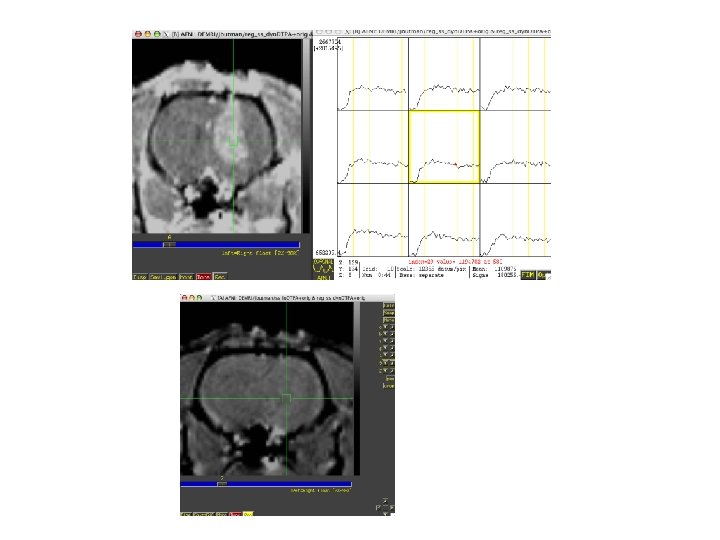

ARN volumeregistered

Steps • Volume register • Identify sagittal sinus ROI can calculate Mp(0) for first

Steps • Volume register • Identify sagittal sinus ROI can calculate Mp(0) for first few TRs, Mp(t) • Calculate Cp(t), Gd concentration in plasma, with nonnegative constraint • 3 d. Automask to limit voxels to brain or specify ROI • Also normalize to ratio of first few TRs and limit voxels of interest to those that change by at least 10% over the average of last five time points • May want to separate blood and tissue with two ROIs to use a single intrinsic relaxivity at a time (Gyrus Finder Plug-in? ) • 3 d. NLfim - calculate fit of Ktrans, kep, fpv given Cp(t), R 1, I, TR to the normalized m(C, T) • m = f(C, R 1, I), C=f(Ct, fpv, Cp(t)), Ct=f(Cp(t), ktrans, kep or Ve) • final fit parameters = Ktrans, kep, fpv for each voxel

----- HISTORY ----================== === History of inputs to 3 dcalc === Input a: 3

----- HISTORY ----================== === History of inputs to 3 dcalc === Input a: 3 dvolreg -prefix barr_vr. nii BARR. nii === Input b: 3 dvolreg -prefix barr_vr. nii BARR. nii 3 d. Tstat -prefix barr_mean 7. nii 'barr_vr. nii[0. . 6]' === Input c: 3 dvolreg -prefix barr_vr. nii BARR. nii 3 d. Tstat -prefix barr_mean 7. nii 'barr_vr. nii[0. . 6]' 3 d. Automask -prefix barr_mask barr_mean 7. nii ================== 3 dcalc -a barr_vr. nii -b barr_mean 7. nii -c barr_mask+orig -prefix barr_norm 7 m. nii -datum float -expr 'a*c/b' 3 d. NLfim -input barr_norm 7 m. nii -signal demri_3 -ignore 0 -noise Zero -sconstr 0 0 0. 05 -sconstr 1 0 0. 05 -nabs -mask barr_mask+orig -nrand 10000 -nbest 10 -voxel_count -sfit barr_sfit 6 -jobs 2 -progress 10000 -bucket 0 nl 6. out Output prefix: nl 6. out